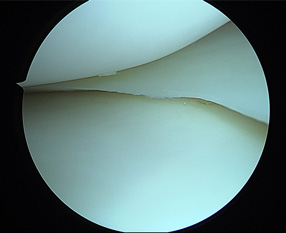

• 画像:正常な半月板関節鏡画像(内側)

正常な半月板関節鏡画像(内側)

• 画像:正常な半月板関節鏡画像(外側)

正常な半月板関節鏡画像(外側)

• 画像:損傷後内側半月板関節鏡画像

損傷後内側半月板関節鏡画像

• 画像:部分切除後内側半月板関節鏡画像

部分切除後内側半月板関節鏡画像